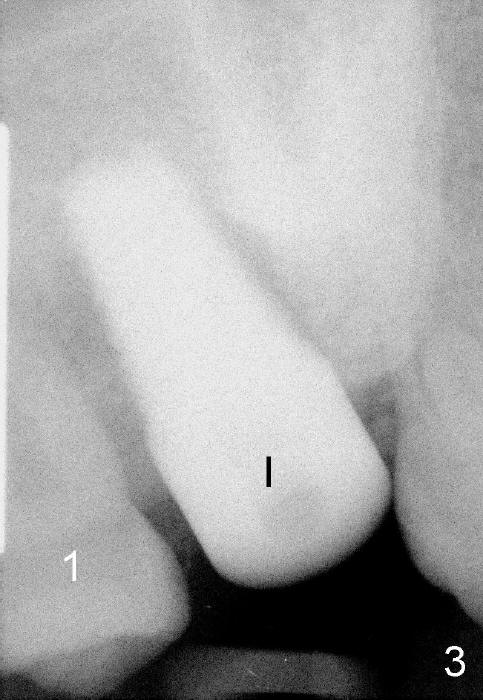

A 48-year-old lady is a dental phobic and has generalized chronic periodontitis. Bone loss around the tooth #2 has been severe for the last 5 years (Fig.1,2 *). Finally she agrees to have #2 (symptomatic) extracted and immediate implant placed (Fig.3 I). A 7x17 mm implant has to be used to achieve primary stability. The remaining buccal and lingual gaps are filled with allograft and membrane (Fig.4 *). Fig.5 shows that there is a space between the tooth #1 (asymptomatic) and the immediate implant (I). The wound/socket is protected by applying perio dressing around an abutment (Fig.6 A). Postop the patient is pain free; the perio dressing dislodges by itself. She returns 3.5 months later for restoration; but the tooth #1 has shifted mesially (Fig.6 arrow). The patient is not so willing to have #1 removed. Bands and bracket are placed in the neighboring teeth including a provisional crown to move the shifted tooth (with mobility) distally (Fig.7,9). The 2nd reason for #1 shifting is abnormal occlsual scheme on the right posterior region (Fig.8); mobility of #1 is the 1st one. The 3rd one is probably bruxism. In 5-6 weeks, the tooth #1 has moved to a desirable position (Fig.10, as compared to Fig.3,5). There is enough space for restoration (Fig.11,12).